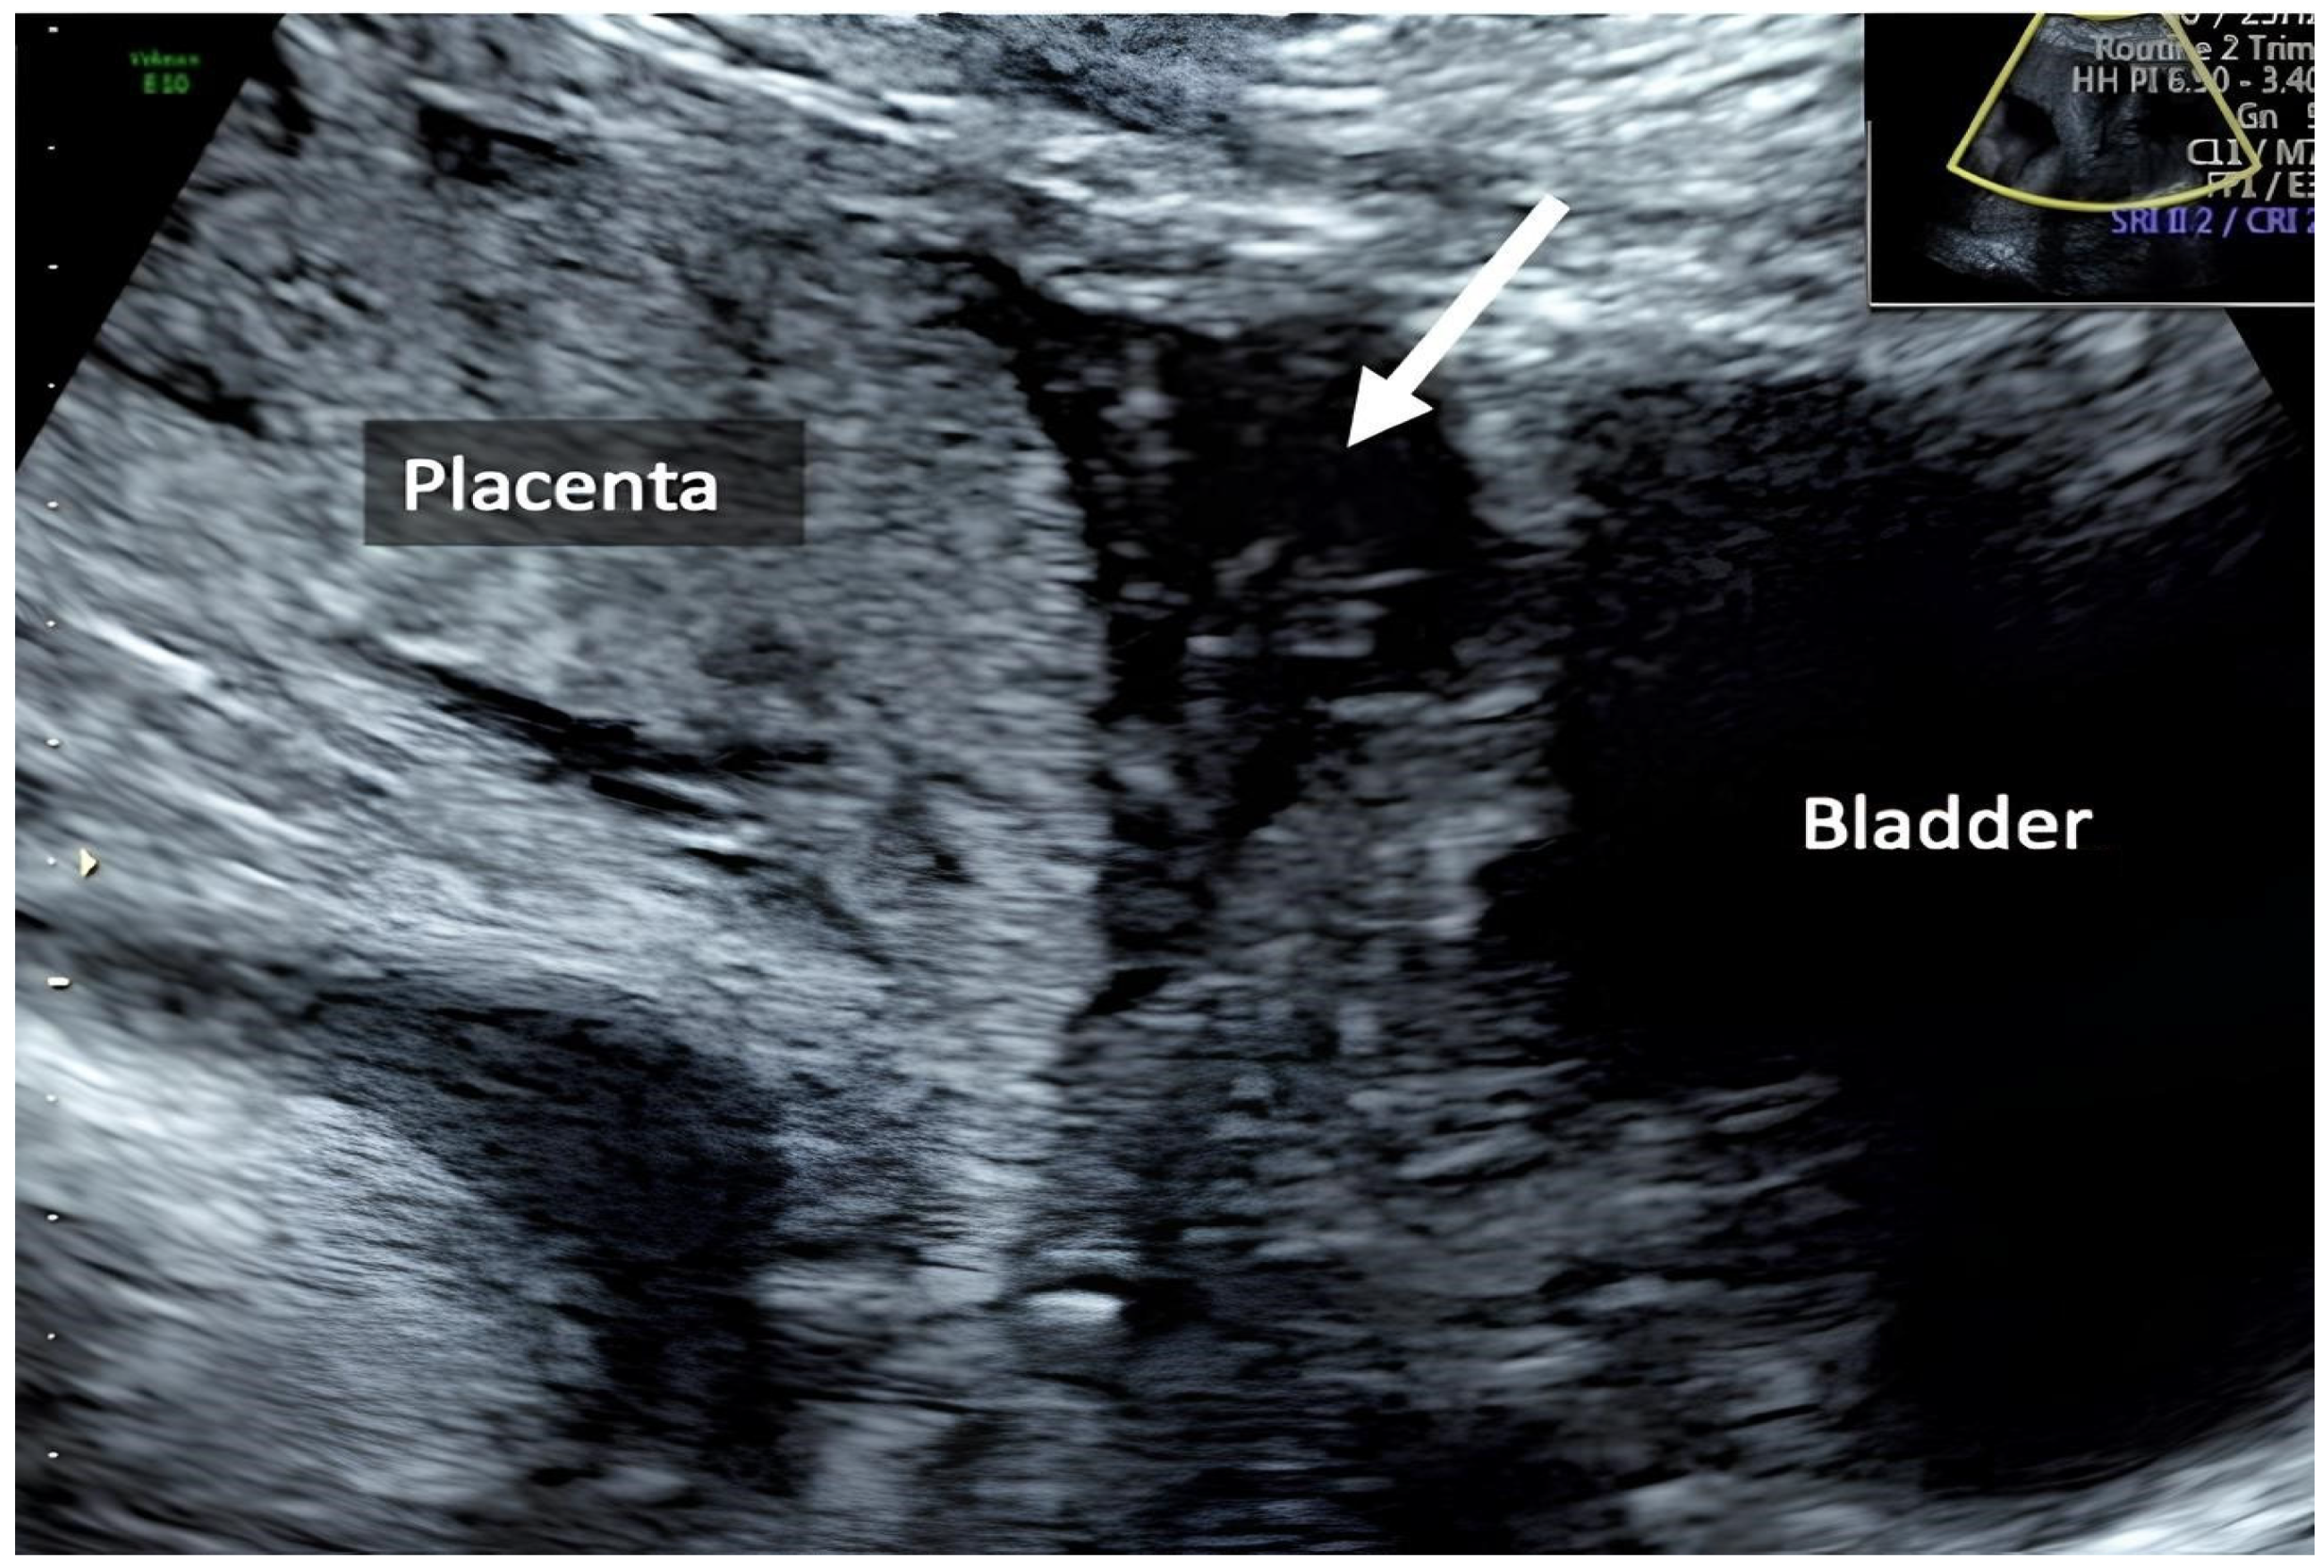

| Zermano S. et al. | 2024 | 29 1/7 | No | Yes | Yes | Yes | |